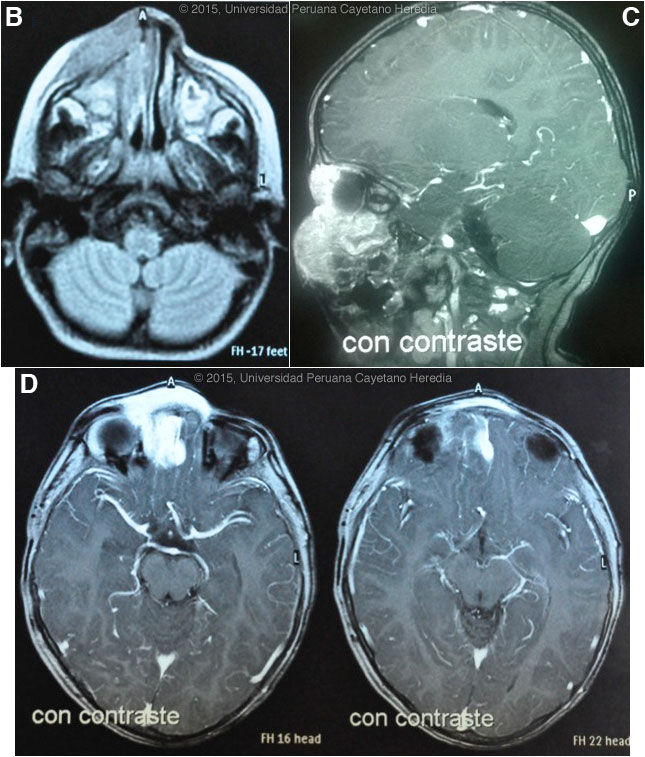

Epidemiology: Born and lives in the district of Mórrope, department of Lambayeque in the coastal desert of Perú, in a house made of adobe, with no running water or sewage. Drinks well water. Contact with cats, dogs, pigs and chickens. No history of fresh-water exposure in lakes, ponds or rivers. No known TB contact. No relevant family history, no similar illnesses in the community. Physical Examination: Percentile weight for height: (50-75); percentile weight for age: (25-50). Afebrile, pulse 128, respirations 28. An infiltrative red-violaceous lesion was observed on the nose that extended to the right chin and affected the inner angle of the upper and lower right eyelids, with thickening of the right nasal mucosa and marked obstruction of the lumen [Image A]. Deviation of the globe, but ophthalmology and neurology consultants found normal ocular movements, normal visual acuity, and normal retinal and vitreous examinations. No lymphadenopathy. No oral or mucosal lesions. The rest of the exam was normal. Laboratory Examination: Hematocrit: 31%, hemoglobin: 9.5 g/dL, platelets: 315,000. WBC 6,900 (normal differential, no eosinophils); normal liver function tests. CT scan of the nasal sinuses revealed an extensive process in the right maxillary sinus extending to the ethmoidal and right orbital areas, compatible with lymphoma or rhabdomyosarcoma. MRI disclosed an infiltrative process of the soft tissues surrounding the nose but extending to the nasal septum, maxillary and ethmoidal sinuses, and right orbital area, infiltrating the medial and inferior rectal muscles and brain parenchyma [Images B, C, D].